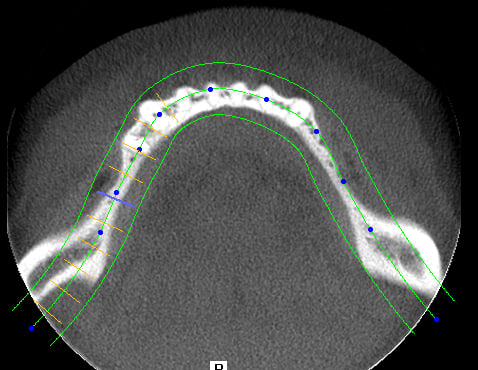

Au maxillaire il faut faire une implanto totale et stt ne pas garder les canines

A la mandibule faut disker mais ça va

PS il faut d abord faire réaliser des modèles stéréolithographiques par Materialise pour se prononcer au final

1. les palques ont une assisse énorme par rapport à 7 cylindres

2. la résorption centripède du maxillaire le rend trop petit pour en poser plus

De plus malgré le grand overjet , on a qd même un implant central qui soutient l arc incisif, même s il est 2 cm en arrière de la ligne des dents

> 2. la résorption centripède du maxillaire le rend trop petit pour en poser plus